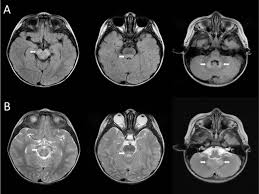

Differential Diagnosis Of Temporal Lobe Lesions With Hyperintense Signal On T2 Weighted And Flair Sequences Pictorial Essay

Differential Diagnosis Of Temporal Lobe Lesions With Hyperintense Signal On T2 Weighted And Flair Sequences Pictorial Essay from www.scielo.br

The basal ganglia are usually spared. Mri is the diagnostic modality of choice abnormal in 90%; Hsv encephalitis | radiology case | radiopaedia.org. Axial t2 prominent swelling, increase t2 signal involving the left temporal lobe and insular cortex. For a general discussion, and for links to other system specific manifestations, please refer to the article on hydatid disease. Herpes simplex (hsv) encephalitis is the most common cause of fatal sporadic fulminant necrotizing viral encephalitis and has characteristic imaging findings. Herpes simplex virus (hsv) is a human herpesvirus that causes hsv encephalitis (hse), which is the commonest fatal sporadic encephalitis in humans. Hse may result from primary infection or reactivation from latency, and it frequently involves frontal or temporal lobes, as well as the brain stem. The differential diagnoses include limbic encephalitis (paraneoplastic), gliomatosis cerebri, and status epilepticus. A brain biopsy was performed and the histology was consistent with encephalitis. For a general discussion, and for links to other system specific manifestations, please refer to the article on hydatid disease. Cerebral malaria is a rare intracranial complication of a malarial infection. Bilateral temporal lobe t2 hyperintensity refers to hyperintense signal involving the temporal lobes on t2 weighted and flair imaging.

For a general discussion, and for links to other system specific manifestations, please refer to the article on coccidioidomycosis. But changes are not specific for hsv (e.g. Multilocularis, and describes a spectrum of disease involving the spinal cord, the spine, or both. There is also some cortical ribboning seen on dwi. Cerebritis is a term that represents inflammation of the brain in the setting of infection, before the development of a cerebral abscess. Cerebral malaria is a rare intracranial complication of a malarial infection. Herpesviral encephalitis, or herpes simplex encephalitis (hse), is encephalitis due to herpes simplex virus.it is estimated to affect at least 1 in 500,000 individuals per year, and some studies suggest an incidence rate of 5.9 cases per 100,000 live births. Herpes simplex (hsv) encephalitis is the most common cause of fatal sporadic fulminant necrotising viral encephalitis and has characteristic imaging findings.

The differential diagnoses include limbic encephalitis (paraneoplastic), gliomatosis cerebri, and status epilepticus. Ventriculitides) refers to inflammation, usually due to infection, of the ependymal lining of the cerebral ventricles. For a general discussion, and for links to other system specific manifestations, please refer to the article on coccidioidomycosis. Herpes simplex (hsv) encephalitis is the most common cause of fatal sporadic fulminant necrotising viral encephalitis and has characteristic imaging findings. Bilateral temporal lobe t2 hyperintensity refers to hyperintense signal involving the temporal lobes on t2 weighted and flair imaging. For a general discussion, and for links to other system specific manifestations, please refer to the article on hydatid disease. Given the history of fever and seizures coupled with the mri findings of bilateral mesial temporal lobe changes, herpes encephalitis requires clinical consideration. It is most often due to meningitis. Multilocularis.the larval stage is the cause of hydatid disease in humans 1. Spinal hydatid disease is an uncommon manifestation of hydatid disease, caused by the larval stage of echinococcus granulosus, or less commonly e. Terminology cerebritis is essentially the same as encephalitis except that it is used to denote brain par. It is a common finding on brain mri and a wide range of differentials should be considered 1. It is usually bilateral but asymmetrical.